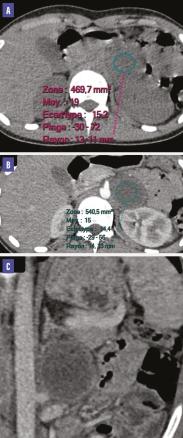

Le scanner réalisé montre une intégrité des glandes surrénales avec présence d’une masse rétropéritonéale gauche, bien limitée, de contours réguliers, de 45 x 40 mm, de densité liquidienne, à paroi épaisse et régulière rehaussée après contraste (figure). L’étude histologique est en faveur d’un paragangliome sans signes de malignité.

Généralement, il s’agit d’une masse bien limitée, hypervascularisée, mais pouvant être kystique, nécrosée en son centre ou calcifiée.2